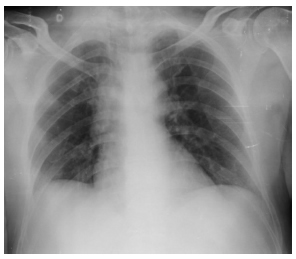

En la radiografía de tórax (Figura 2) se aprecia mediastino ensanchado, opacidades de aspecto nodulillares bilaterales. Se realizó biopsia de lesión cutánea que informo efecto citopático viral y queratinocitos necróticos, lesiones éstas características de la familia herpes viridae.